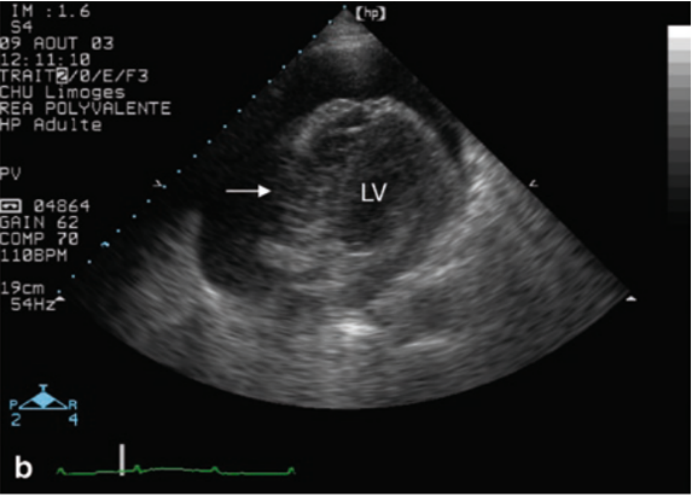

心脏压塞的超声诊断:包括右心腔在吸气时增大的比例下降、右心房收缩期塌陷、右心室游离壁在舒张期塌陷、下腔静脉内径增宽呼吸变化率减低(视频1,图5)。右心房的收缩期塌陷是早期心脏压塞的一个敏感标志,早期阶段敏感性为50%,晚期阶段敏感性可达100%。然而,在右心室充盈压力升高的患者中,如由肺动脉高压或高血容量引起,跨膜压力可能需要更高才能导致心房塌陷,从而降低压缩效应。

图片

5  右心室在吸气时塌陷